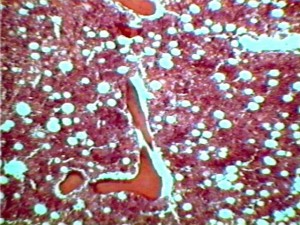

Si tratta di una terapia basata su cellule staminali prelevate dal midollo osseo del paziente e poi miscelate a un gel a base di collagene inserito nei diversi punti di frattura. “Sono sicuro -afferma fiducioso Kent sulla pagine del britannico Daily Mail- che la gamba tornera’ come nuova e io potro’ un giorno scalare la roccia.